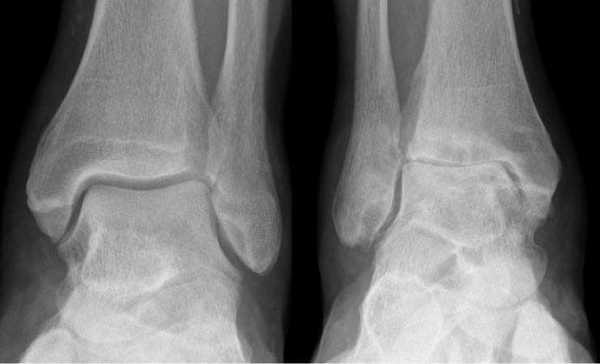

Артроз левого сустава. Суставная щель очень мала.

Наиболее частая патология посттравматического генеза с прогрессирующим течением — остеоартрит. Травму можно вылечить консервативно, а вот артроз голеностопного сустава — это уже неизлечимая патология, которая значительно ухудшает качество жизни человека.

Артроз, в свою очередь, является последствием артрита. Вот такой вот цепной механизм развития сложной клинической ситуации. От травмы до деформирующего остеоартроза (ДОА) несложно дойти за пару-тройку лет. Но если травму несложно вылечить консервативно, то с артрозом голеностопного сустава все иначе - это неизлечимая болезнь, которая критически угнетает качество жизни, негативно влияет на статику и динамику всей конечности.